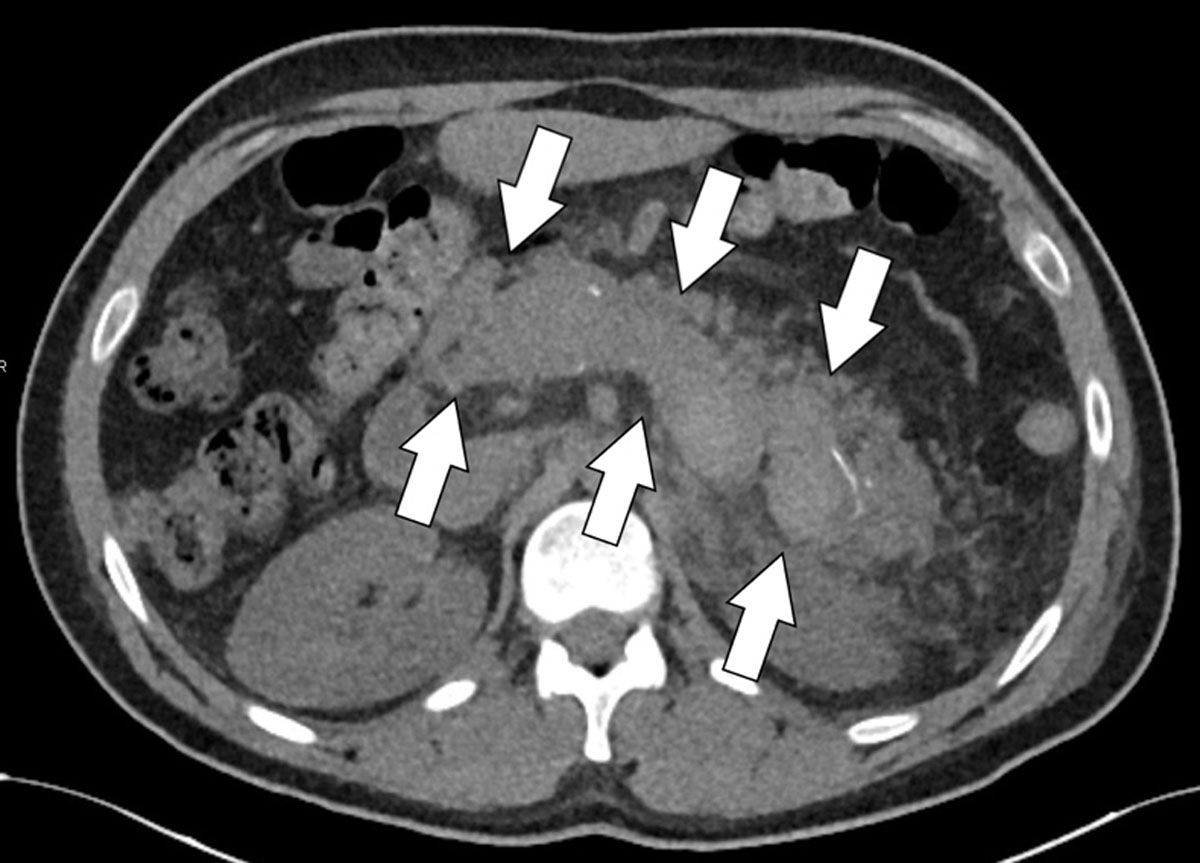

Figure 1a

Axial unenhanced CT-slice revealing a spontaneously hyperdense splenic vein thrombus.